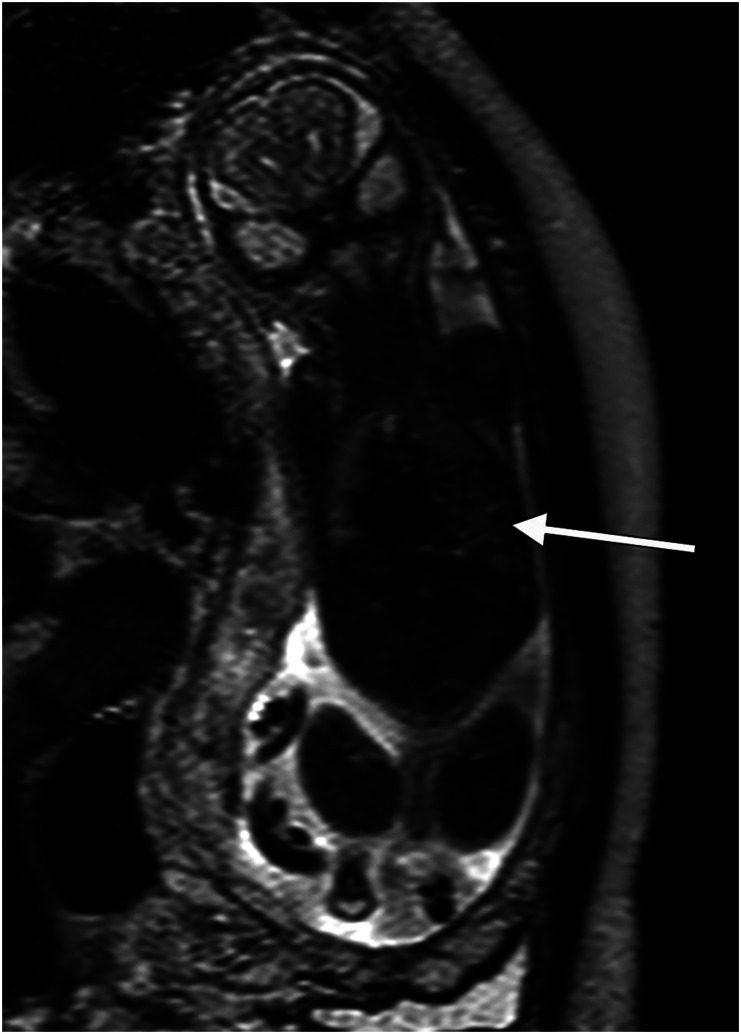

背景:胎儿超声波检查有其局限性,尤其是在患者肥胖或胎粪过少的情况下。核磁共振成像(MRI)可作为补充,但只有少数研究关注妊娠后三个月的检查。目的:验证核磁共振成像作为诊断妊娠后三个月胎儿畸形的补充:这项回顾性研究检索了乌普萨拉大学医院胎儿医学科和放射科 2008 年 1 月至 2012 年 7 月的数据。研究回顾了 121 个胎儿的超声和磁共振成像结果与最终诊断的关系,包括产后随访和尸检结果:结果:在 121 个胎儿中,51 个(42%)确诊或怀疑有中枢神经系统异常,70 个(58%)确诊或怀疑有非中枢神经系统异常。在所有病例中,核磁共振成像为21%的病例提供了额外的信息,但并未改变妊娠管理,而为13%的病例提供的信息改变了妊娠管理。当发现或怀疑中枢神经系统异常时,核磁共振成像为 22% 的病例提供了补充信息,改变了 10% 的病例的治疗方案。非中枢神经系统病例的相应数字分别为 21% 和 16%。在体重指数(BMI)大于 30 kg/m2 的患者(25%)和少腹水患者(38%)中,提供额外信息并改变处理方案的病例比例尤其高。在 5 例 III 类病例中,发现了假阳性超声检查结果:结论:妊娠后三个月的核磁共振成像是超声检查的补充,可提高对胎儿中枢神经系统和非中枢神经系统畸形的诊断率,尤其是在少子水肿或孕妇肥胖的情况下。

Results: Of the 121 fetuses, 51 (42%) had a CNS anomaly and 70 (58%) a non-CNS anomaly diagnosed or suspected. MRI provided additional information in 21% of all cases without changing the management and revealed information that changed the management of the pregnancy in 13%. When a CNS anomaly was detected or suspected, the MRI provided additional information in 22% and changed the management in 10%. The corresponding figures for non-CNS cases were 21% and 16%, respectively. The proportion of cases with additional information that changed the management was especially high in patients with a BMI >30 kg/m2 (25%) and in patients with oligohydramnios (38%). In five cases in category III, false-positive ultrasound findings were identified.

Conclusions: MRI in the second trimester complements ultrasound and improves diagnosis of fetal CNS- and non-CNS anomalies especially when oligohydramnios or maternal obesity is present.